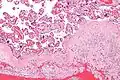

Micrograph of a chronic deciduitis, showing the characteristic plasma cells. H&E stain. |

Chronic deciduitis is a type of long-lasting inflammation that arises in pregnancy and affects the endometrial stromal tissue (decidua).

It is associated with preterm labour.[1] The diagnosis rests primarily on the presence of plasma cells.[2]